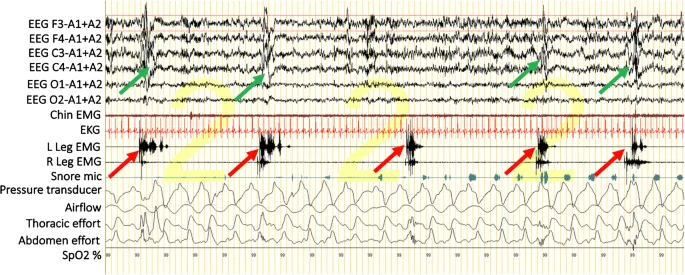

- Diagnosis: Polysomnography (PSG) is the definitive diagnostic tool.

- Diagnostic threshold: PLM index (PLMI) ≥ 15 movements/hour in adults.